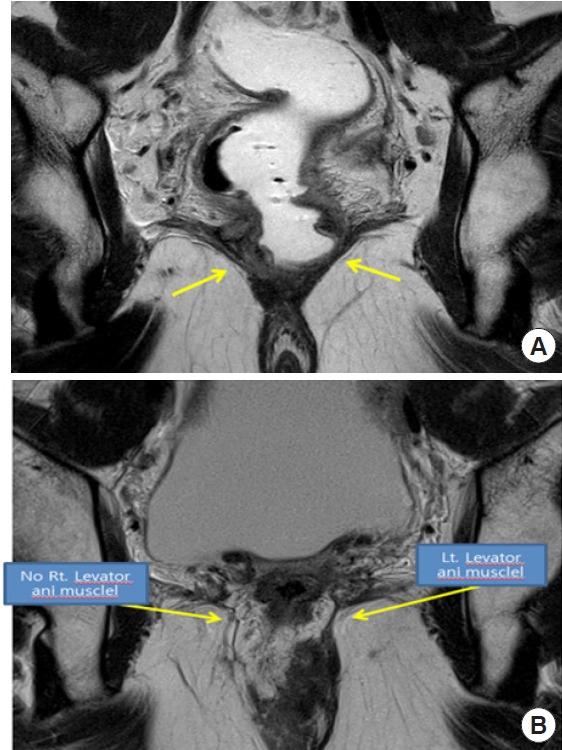

Despite innovative advancements, distally located rectal cancer remains a critical disease of challenging management. The crucial location of the tumor predisposes it to a circumferential resection margin (CRM) that tends to involve the anal sphincter complex and surrounding organs, with a high incidence of delayed anastomotic complications and the risk of the pelvic sidewall or rarely inguinal lymph node metastases. In this regard, colorectal surgeons should be aware of other issues beyond total mesorectal excision (TME) performance. For decades, the concept of extralevator abdominoperineal resection to avoid compromised CRM has been introduced. However, the complexity of deep pelvic dissection with poor visualization in low-lying rectal cancer has led to transanal TME. In contrast, neoadjuvant chemoradiotherapy (NCRT) has allowed for the execution of more sphincter-saving procedures without oncologic compromise. Significant tumor regression after NCRT and complete pathologic response also permit applying the watch-and-wait protocol in some cases, now with more solid evidence. This review article will introduce the current surgical treatment options, their indication and technical details, and recent oncologic and functional outcomes. Lastly, the novel characteristics of distal rectal cancer, such as pelvic sidewall and inguinal lymph node metastases, will be discussed along with its tailored and individualized treatment approach.

尽管有创新性进展,但低位直肠癌仍然是一种管理具有挑战性的关键疾病。肿瘤的关键位置使其易出现环周切缘(CRM)累及肛门括约肌复合体和周围器官的情况,吻合口延迟并发症的发生率很高,且存在盆腔侧壁或极少出现的腹股沟淋巴结转移风险。在这方面,结直肠外科医生应意识到全直肠系膜切除(TME)操作之外的其他问题。几十年来,为避免CRM受损而引入了经肛提肌腹会阴联合切除术的概念。然而,低位直肠癌深部盆腔解剖的复杂性以及视野不佳导致了经肛全直肠系膜切除术的出现。相比之下,新辅助放化疗(NCRT)使得在不影响肿瘤学疗效的情况下能够实施更多保留括约肌的手术。NCRT后显著的肿瘤退缩和完全病理缓解在某些情况下也允许采用观察等待方案,现在有了更确凿的证据。这篇综述文章将介绍当前的手术治疗选择、其适应证和技术细节,以及近期的肿瘤学和功能结局。最后,将讨论低位直肠癌的新特征,如盆腔侧壁和腹股沟淋巴结转移,以及其针对性的个体化治疗方法。